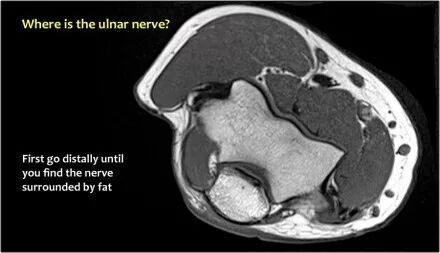

尺神经:在这里,我们看到了肘管内的尺神经。尺骨侧支带的后带形成隧道的底部,而支持带形成屋顶。

当他们将尺神经带出隧道时,他们把它放在哪里,它可以是皮下,肌肉下或肌肉内。

因此,当我们回到图像时,您会发现很难找到神经。任何这些皮下结构都可以是转位神经。一种方法是远端跟随结构,直到你发现远端的尺神经位于由脂肪包围的前臂近端的正常位置。然后当你向近端跟随它时,你会发现这是皮下移位。

在这种情况下,有神经炎。神经增大。在T2W图像上有高信号。另一个标志是在矢状图像(箭头)上看到的束的不均匀扩大。